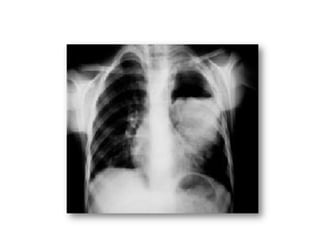

3.1.Circonstance de découverte

3.1.2. Phase KHP ROMPU:

• RX thorax ds les suites immédiates montre:

- des opacités pulmonaires multiples diffuses

et bilatérales en réaction à la libération des

toxines parasitaires

- persistantes pendant quelques jours

traduisant un syndrome de Löeffler.

c) Rupture dans la plèvre ou hydatidothorax :

• Rare , peut s’installer à bas bruit

• Tableau dramatique avec douleur, dyspnée et

cyanose aggravées par un choc anaphylactique.

• aspect « eau de roche « parfois teinté de bile

en cas de KHF rompu dans la plèvre.